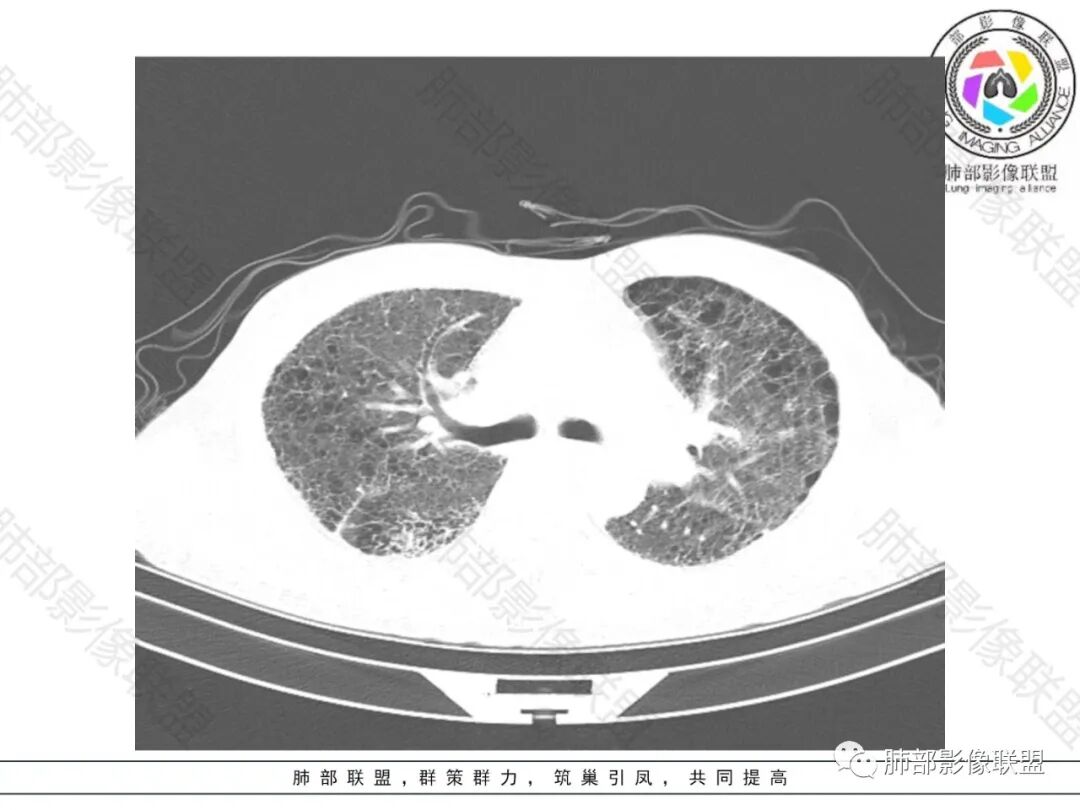

双肺慢支肺气肿。右肺下叶大片状影,支气管狭窄,枯枝状。间杂网格状影,实变影(与胸膜糊墙),叶间裂膨隆。右肺门增大。增强后右下肺片状影内血管束失去正常形态,边缘模糊。实变影不均匀强化。纵隔及右肺门多组淋巴结肿大,其中右侧10、11、12组淋巴结肿大内见液化。考虑肺炎型肺癌并感染?不典型结核待除外。左下小片影?(层面不全)。

老年男性的病人。慢性的咳嗽憋喘为主的症状,慢性的病程。临床ca199明显的增高,癌胚抗原升高。白细胞增高提示有肺部感染的。影像学表现两肺弥漫性的网格状改变。而病变又集中在右肺下叶。右肺门见一个大结节的病灶,内部有片状坏死,不均匀的强化,邻近的支气管变窄,周围的肺组织呈大片状的实变影。纵隔淋巴结多个肿大。这样的影像学考虑右侧肺门旁的恶性病变。鳞癌或者粘液性腺癌,伴纵隔淋巴结转移,右肺下叶的癌性淋巴管炎,两肺慢性的间质性肺炎。

老年男性,反复咳嗽咳痰喘憋8年,加重10天,发热半天。白细胞计数明显升高(存在细菌感染可能),CEA、CA19—9升高(肺癌或间质性肺疾病引起可能)。痰培养见肺克。CT;双肺弥漫小叶间质、中轴间质增厚,胸膜下肺气肿,右肺门及右下叶可见实变影,边界模糊,内支气管走形僵硬,部分见蜂窝样改变,增强后实变区可见低密度区(粘液?),叶间裂膨隆,纵隔及右肺门见肿大淋巴结,右肺门淋巴结内见坏死。存在感染,但单纯感染难以解释支气管走行僵硬、实变内的低密度病灶,考虑恶性伴感染,肺炎性肺癌或黏液腺癌。

病史八年,慢支病史,两肺中轴间质及小叶间隔增厚,可见胸膜下线,提示有间质性肺病ulp,右下肺大片实变,叶间裂膨隆,纵隔淋巴结肿大,实变内GGO以网挌为中心,强化有血管造影征,实变内支气管走行僵直〈枯树枝征)并扭曲扩张,可见低密度粘液拴,综合考虑为1,右下肺炎性肺癌,粘液腺癌可能性大,2,uip

整个背景是一个肺气肿并间质纤维化,肺气肿以上肺为主(有些地方分不清到底是小叶中心或间隔下肺气肿伴间隔增厚还是蜂窝),左肺下叶正常结构消失,以弥漫网格为主,应该没有多少正常肺功能组织。右肺下叶肺动脉栓塞,再往下几层应该是肿大淋巴结并坏死。右肺下叶的病变考虑粘液性腺癌, 需与感染鉴别(有没有可能是肺梗死呢?)

2.影像表现:肺气肿背景,右肺下叶呈现明显网格影及蜂窝影、枯枝征,边缘膨隆、叶间裂向前方推移。病灶密度不均,前份见不规则片状实性密度区,实性部分轻度强化,边界不清,周边特征掩盖不清。支气管主要分支显示,呈枯枝征。纵隔窗病灶密度偏低,病灶内血管影边缘稍显模糊,未见明显液化坏死区。

3.综合分析:临床方面:慢性病程、急性发作,呼吸道症状伴发热,炎性指标升高,提示存在感染可能;CA199升高,但相对特异性不高。影像双肺气肿,右肺下叶蜂窝状改变明显,夹杂实变密度区,支气管相关但未见阻塞,较常见于感染性病变,如G-杆菌感染等。蜂窝影什么时候出现我们不得而知,实变区周边特征掩盖不清。

因为有肺气肿背景、有蜂窝,周边特征及张力等都不能作为判断依据或参考。单肺叶蜂窝影伴实性密度区被确诊为肺腺癌的例子已不少见,敬请留意。